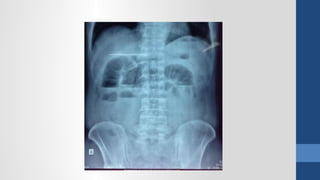

2. Ch n đoán hình nhẩ ả

Xquang b ng đ ng không chu n bụ ứ ẩ ị

2. Ch nđoán hình nhẩ ả Siêu âm Xquang b ng đ ng không chu n bụ ứ ẩ ị CT Scanner N i soi thăm dòộ

• #64 Xquang - Viêm phổi (thâm nhiễm phổi), - Tắc ruột (mức nước hơi), - Thủng tạng rỗng (hơi tự do trong bụng), - Sỏi thận và hệ niệu (vôi hóa bất thường), - Viêm RT (fecalith)?, - Thoát vị kẹt (ruột trồi khỏi giới hạn ổ bụng)?, - Nhồi máu mạc treo (hơi trong TM cửa), - Viêm tụy mãn (vôi hóa tụy), - Viêm tụy cấp (sentinel loop, colon cutoff), - Phình ĐM (bờ vôi hóa)?, - Tụ máu hoặc áp xe sau phúc mạc (mất bóng cơ psoas), Siêu âm - Những bệnh vùng chậu (u buồng trứng, Viêm RT cấp, thai ngoài tử cung, thai trong tử cung), - Sỏi mật (túi mật, đường mật), - Gan (áp xe, bướu gan), - Thận (ứ nước, sỏi), - Dịch tự do trong bụng (xuất huyết nội, dịch viêm, ascites) CT Scan: - có giá trị định bệnh cao hơn SA nhưng không nên dùng cho BN nữ đang mang thai hoặc cho trẻ em. - Viêm đại tràng thiếu máu (dấu ấn ngón tay trên thành đại tràng). &amp;lt;number&amp;gt;